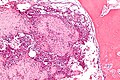

Chondroblastoma. H&E stain. | |

| LM | abundant (chondroid) extracellular material, chondroblasts (variable nuclear morphology (ovoid, folded or grooved), moderate-abundant eosinophilic cytoplasm), +/-calcifications surrounding the cell nests ("chickenwire" appearance) - classic feature, +/-giant cells |

- +/-Calcification surrounds the cell nests ("chickenwire" appearance) - classic feature.

- +/-Giant cells.

- Not infrequently associated with an aneurysmal bone cyst (33%).[3]